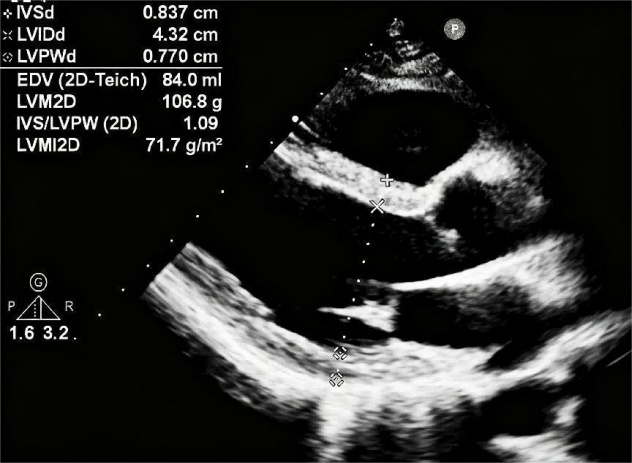

超声报告上,查看室间隔、左室后壁、左心室舒张末内径等指标,是我们判断心脏变形的第一步。通过上述指标,能计算出心脏是否变胖,也就是左室质量指数,它是高血压患者不良事件的单一且重要的预测指标。发现变胖之后,可以结合相对室壁厚度来判断身材改变的类型,身材不同,发生心血管事件的风险也不同。